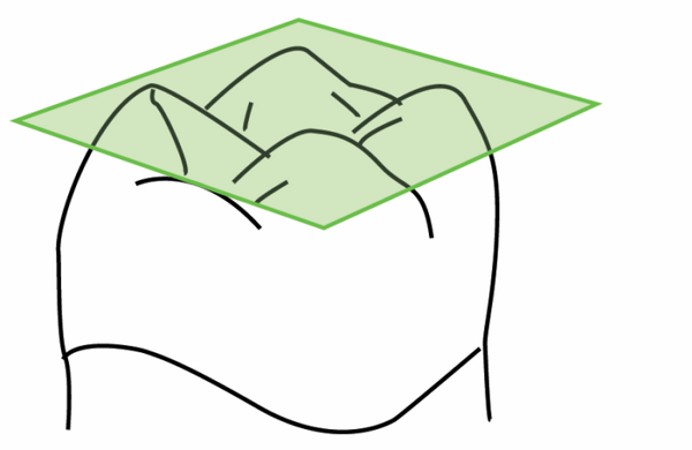

Primera Parte RESUMEN: La alta complejidad inherente a los procedimientos de Rehabilitación Oral, obligan al profesional que la ejerce a basarse en parámetros multidisciplinarios, a veces lo suficientemente intrincados que hacen imposible la práctica de la misma, sin la presencia en su mente de una clara concepción de la Oclusión. The extreme complexity of Oral Procedures, make it imperative for the working professional to rest on multidisciplinary parameters, sometimes so complex that make impossible its practice without the presence of a clear idea of Oclusion. DESARROLLO Suele ser sumamente árido el abordaje de un tema como Oclusión, desde la perspectiva de nuestro diario trabajo ,con todo el strees que este conlleva, con toda la lucha que significan citas, honorarios, diferentes personalidades de los pacientes, inquietudes de los mismos, etc. «LA MEJOR OCLUSIÓN ES LA QUE TIENE LA MEJOR DESOCLUSIÓN» Básicamente, podemos como desde hace ya muchos años se viene haciendo; clasificarlos en: A)Determinantes Posteriores (fijos) Más contemporáneamente, en: I-Mecanismos Primarios: A.T.M. GUIA ANTERIOR INCLINACIÓN DEL PLANO OCLUSAL CURVA SAGITAL DE SPEE FORMA DE LA ARCADA III-Mecanismos Elementales CRESTAS TRIANGULARES INTERNAS Analicemos cada uno de ellos: Es evidente, que la reproducción de las características de la A.T.M., en nuestro aliado fundamental, el Articulador; es imprescindible. Partiendo de la premisa de obtener una OCLUSIÓN MUTUAMENTE PROTEGIDA, para luego arribar al concepto de OCLUSIÓN MUTUAMENTE COMPARTIDA, concepto este que desarrollaremos durante el transcurso de las distintas entregas, analizaremos cada uno de los FACTORES DETERMINANTES DE LA OCLUSIÓN. El primero de ellos, por ser fijo e invariable, solo diremos que: son sus INCLINACIONES PLANARES, o sea : A-INCLINACIÓN DE LA TRAYECTORIA CONDILEA C-BENNET INMEDIATO articuladores totalmente ajustables) D-DISTANCIA INTERCONDILAR. En cuanto a la GUÍA ANTERIOR, mecanismo primario y por supuesto anterior, provee al cuerpo mandibular; del camino a recorrer durante las excursiones protrusivas y lateralidades, a través del vínculo entre las piezas dentarias anteriores, superiores e inferiores. En un corte sagital, podemos observar la relación entre estos donde vemos que se vinculan sin entrar en un contacto franco, sino más bien en una relación de vencindad muy intima a la que llamamos: PUNTO DE ACOPLAMIENTO. Otros factores fundamentales de la GUÍA ANTERIOR son : A-ALTURA FUNCIONAL B-PUNTO DE ACOPLAMIENTO En cuanto a los SURCOS, sabemos que durante una Transtrusión, las cúspides fundamentales generan surcos sobre las piezas que antagonizan. Dichos surcos proveen de una vía de escape a las cúspides antagonistas para evitar colisiones, con las indeseables fuerzas laterales cuya gravedad ya conocemos. MECANISMOS SECUNDARIOS La CURVA FRONTAL DE WILSON, se observa invertida a nivel de los caninos y de los primeros premolares. El PLANO OCLUSAL, en realidad no es ningún plano, sino la sumatoria de muchos MICROPLANOS, los cuales individualmente pueden constituir factores presentes en la OCLUSIÓN, pero auténticos problemas para la DISCLUSIÓN. La CURVA SAGITAL DE SPEE, denominada originariamente de BALKWIL-SPEE, fue concebida como una curva. El cuarto factor SECUNDARIO: el ANCHO DE LA ARCADA, es evidente que variando los ejes de rotación , alrededor de las diferentes distancias ;cambiará la dirección de los escapes (surcos), de los elementos que en el se muevan (cúspides). MECANISMOS ELEMENTALES Los CUATRO NIVELES DE OCLUSIÓN y las CRESTAS TRIANGULARES INTERNAS, constituyen de por si, la herramienta ejecutora de las funciones gnáticas. A- ELEVACIONES 1-Puntas Cuspídeas B-DEPRESIONES 1-Fosas SURCOS DE DESARROLLO De las CRESTAS TRIANGULARES INTERNAS, acentuamos su importancia en ellas dado que son las efectoras finales de la molienda, y su triangularidad debe tener su base partiendo del surco y su vértice terminando en la Punta Cuspídea, condición importante para evitar colisiones durante la transtrusión (movimiento de lateralidad ). EFECTOS DE LA VARIABILIDAD DE LOS FACTORES DETERMINANTES DE LA OCLUSÍON Cada uno de los determinantes influye aumentando o disminuyendo tanto la DESOCLUSIÓN como la ALTURA CUSPÍDEA INCLINACIÓN DE LA TRAYECTORIA SAGITAL INCLINACIÓN DEL PLANO OCLUSAL RADIO DE CURVATURA DE LA ÁNGULO DE LA TRAYECTORIA ALTURA DEL PUNTO DE LATERO SURTRUSIÓN / MOV. DE BENNET INMEDIATO CURVA FRONTAL DE WILSON SURCOS BIBLIOGRAFÍA Dibujos y esquemas tomados del libro: Oclusión Orgánica…un camino hacia la Rehabilitación Oral. 1)William Mc Horris,B.S.,D.D.S. Oclusión. Con especial énfasis sobre :El rol funcional y parafuncional de los dientes anteriores. 2)Von Spee , Craff(Anatomista alemán, describió la curva de compensación de la articulación de molares y premolares).CURVA DE SPEE 1.89 3)Stuart,D.»Some aspects of the inervation teeth.»Procedings of Royal Society of Medicine.20:1675,19274)Muhleman,H. y Savdir,S»Tooth movility-its causes and significance»Journal of Periodontology ,36:153,Marzo ,Abril,1965. 4)Muhleman,H. Y Savdir,S»Toothmovility its causes and significance» Journal of Periodontology,36:153,marzo,abril,1965. 5-Oclusión y Diagnóstico en Rehabilitación Oral. 6-Anatomia Odontológica. -A contribution to the study of the movementes of the mandible. 8-Celenza F.W, Nadeskin J.F.,Oclusión.Situación actual. 9-D´Amico 10-Dawson P.E. 11-Huffman -Regenos. 12-Hobo S.-Takayama H.A. 13-Lucia V.O 14-Mc Horris. 15-Mc Horris. 13-Posselt U. 16-Stuart C. 17-Vartan Veshnilian

Múltiples son los factores que influyen sobre la morfología y función de las caras oclusales. Los hay de importancia absoluta y determinativa, y algunos ;cuya influencia es más relativa.

No obstante todos aquellos elementos dinámicos que influyen sobre la función gnática, ponen su acento en las formas oclusales, y; como devolución ,serán luego estas formas quienes guíen el camino por donde migre la mandibula.

CUATRO NIVELES DE LA OCLUSIÓN